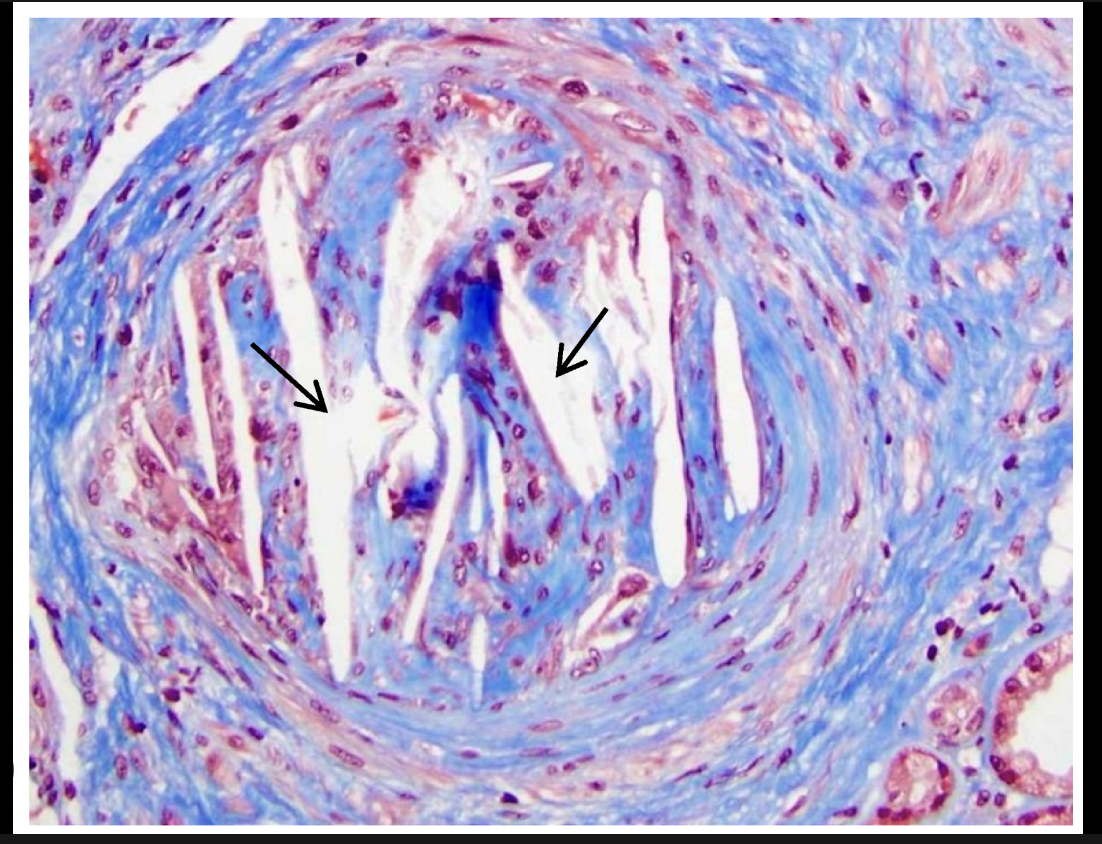

Amyloidosis (AA amyloid)

diagnose with fat pad or rectal targeting blood vessels; biopsy with congo red stain